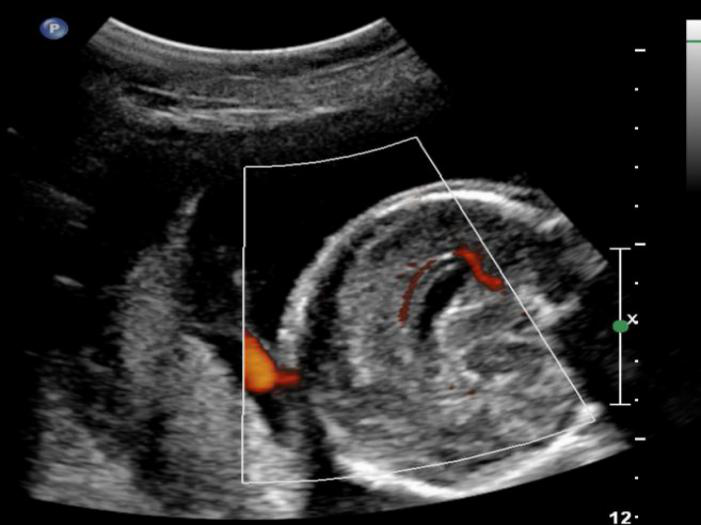

煊流成像技术:SlowflowHD:快速、直观显示微小血管

能否看清子宫内膜息肉的微小血管决定了诊断的准确性

胼胝体周动脉超低速血流灌注状态

Radiantflow:更少的频闪和增强的血管边界显示